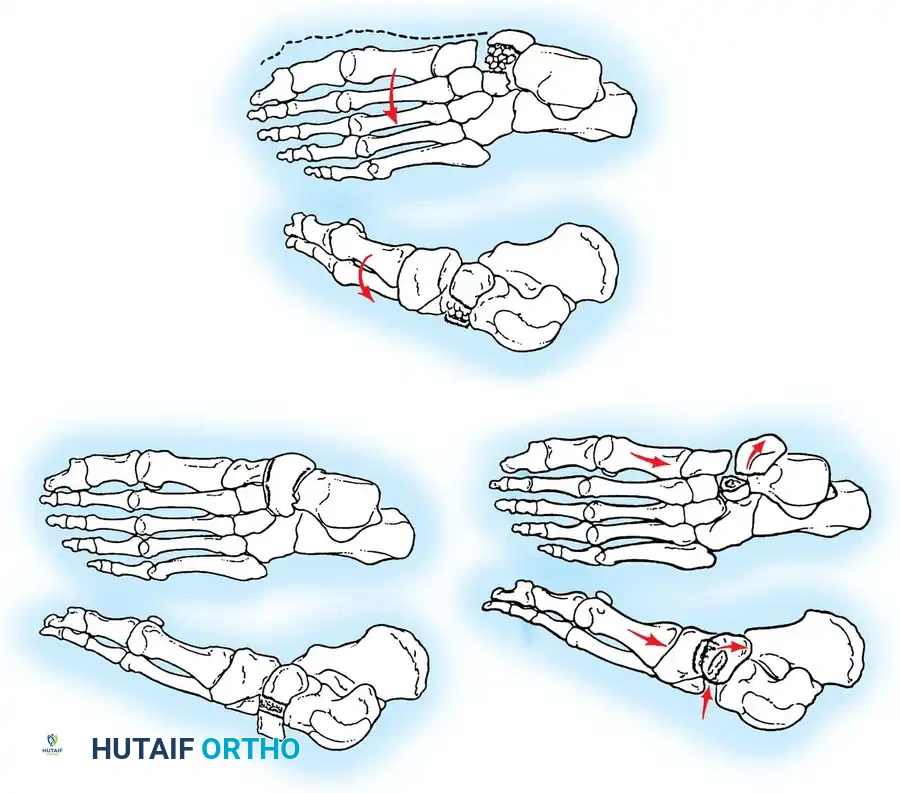

Fig. 33-204 Four types or stages of osteochondral fractures (osteochondritis dissecans of talus). Stage I, “blister”; stage II, elevated fragment but attached; stage III, fragment detached but still in crater; stage IV, displaced fragment.

Morphologically and etiologically, medial and lateral lesions differ significantly:

- Lateral Lesions: Almost exclusively caused by trauma. They are typically thin, wafer-shaped, and resemble acute osteochondral shear fractures. They are more prone to persistent symptoms and degenerative changes.

- Medial Lesions: While many are traumatic, a significant portion have no history of trauma (suggesting true osteochondritis dissecans or ischemic etiology). Medial lesions are typically deep and cup-shaped.

Fig. 33-205 Morphology of medial and lateral lesions. Lateral lesions are typically shallow and wafer-shaped, while medial lesions are deeper and cup-shaped.